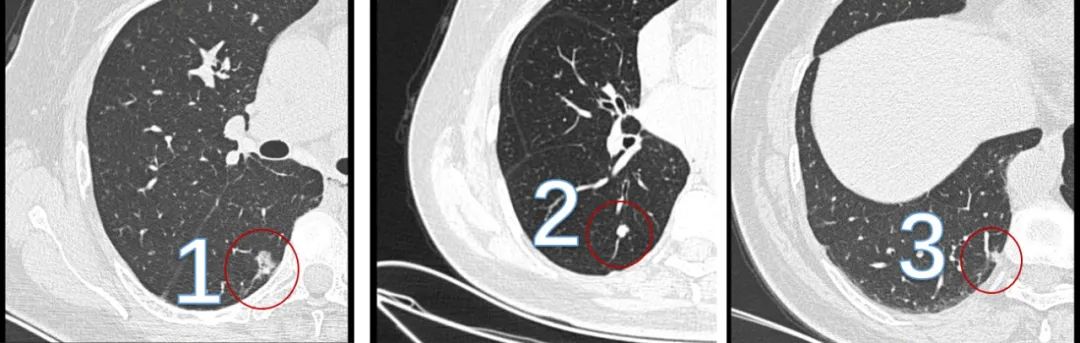

竟然有三個結節。第一個已經很大了,接近2cm,形態就不太像好東西;第二個雖然是實性結節,好在邊緣比較光滑,像是良性的;第三個雖然比較小,但也是混合磨玻璃結節,還有實性成分,密度不低。

老媽右下肺的三個結節